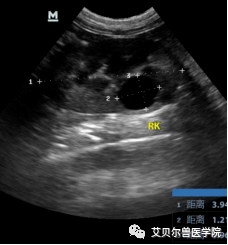

猫多囊肾的超声表现

图片尺寸228x245